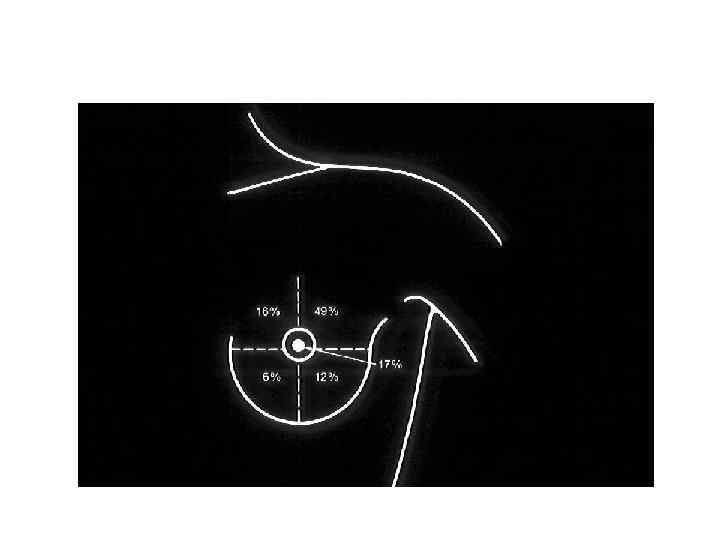

Лечение рака молочной железы Комплексное 1 Хирургическое – радикальная мастэктомия 2 Лучевая терапия – Лечение рака молочной железы Комплексное 1 Хирургическое – радикальная мастэктомия 2 Лучевая терапия – перед и (или) после операции 3 Полихимиотерапия – перед и (или) после операции 4 Антиэстрогены (тамоксифен)

Радикальная мастэктомия Радикальная мастэктомия